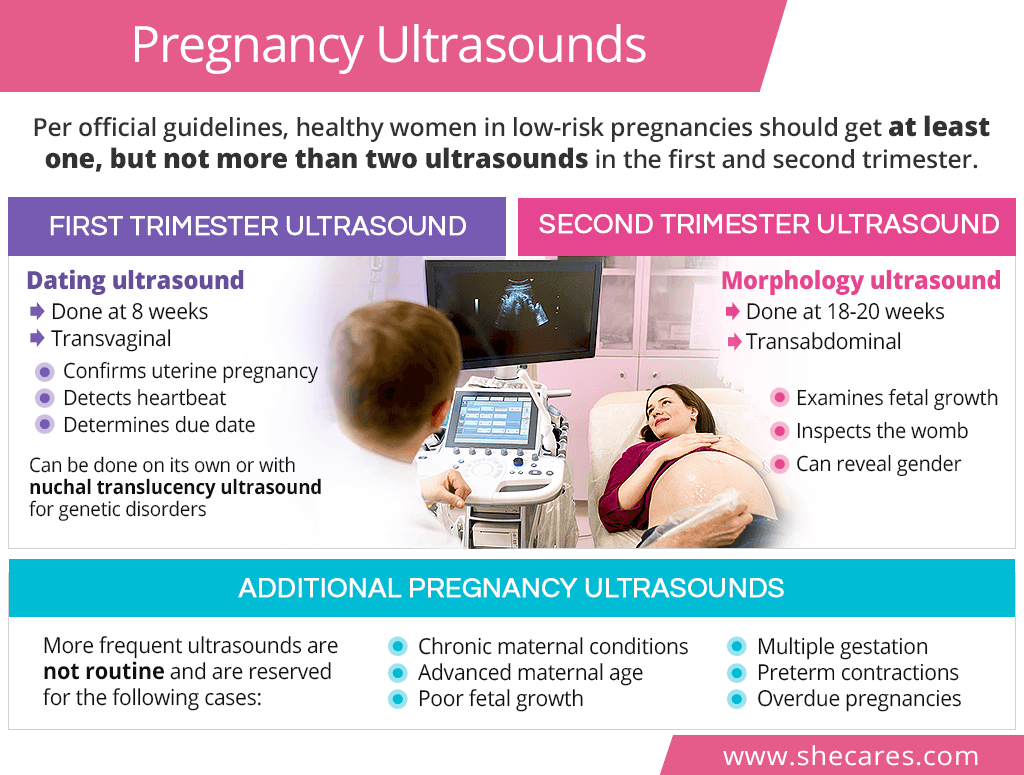

A guide to saline sonograms. Infertility affects men and women equally. How to prepare for an ultrasound during pregnancy.

13, her mother was standing outside in the parking lot, begging a woman at a new. The test can help a healthcare provider diagnose. What is a pregnancy ultrasound?